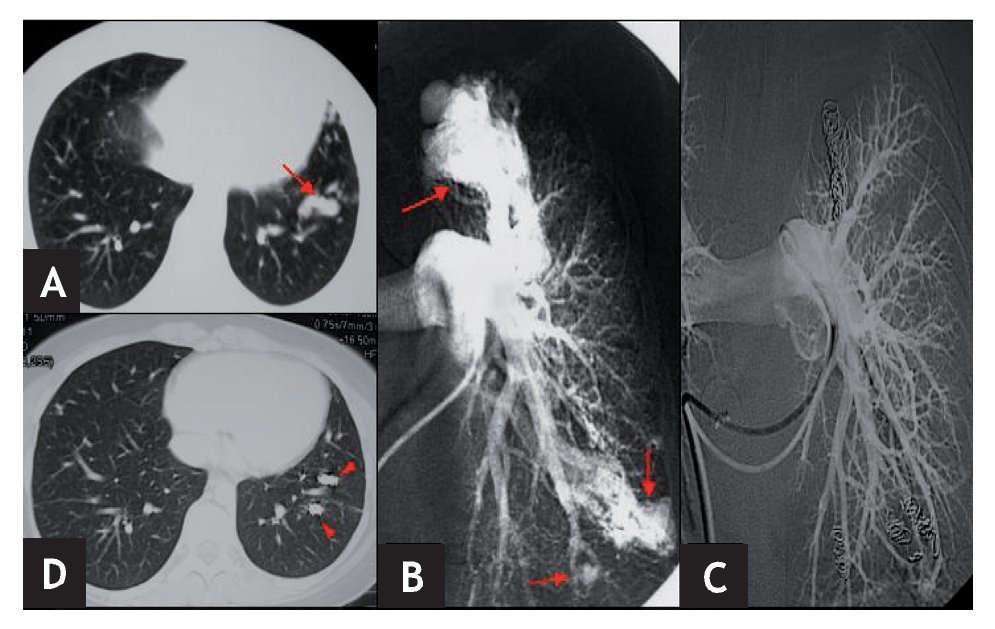

En 5 de los 6 pacientes se lograron cateterizar las ramas de aporte a la MAVP, procediéndose a su embolización y cierre (figs. 1 y 2). En el paciente restante, que presentaba malformaciones múltiples, no fue posible embolizarlas todas. Esto se debió a la imposibilidad de cateterizar algunas de las ramas de aporte porque, al encontrarse muy próximas al corazón, los latidos cardíacos movilizaban el catéter haciéndolo inestable e impidiendo la introducción segura y controlada de las espirales metálicas.

Figura 2 Paciente n.º 3. A) TC torácica donde se observa un grueso vaso pulmonar en língula. B) Angiografía pulmonar izquierda selectiva donde se aprecian varias malformaciones arteriovenosas pulmonares (MAVP) en LSI y língula de tipo complejo (una rama aferente gruesa y múltiples venas eferentes) (flechas). C) Angiografía pulmonar izquierda selectiva postembolización concoilsdonde se observa exclusión completa de todas las MAVP. D) TC torácica de control a los 37 meses postembolización. Obsérvense loscoils (cabezas de flecha) y la ausencia de opacificación de las MAVP.

El seguimiento de los pacientes ha sido clínico en todos los casos y, en 4 de ellos, también radiológico mediante TC de tórax. Todos los pacientes se encuentran asintomáticos tras un período de seguimiento medio de 46 meses (rango, 25-98) y en los 4 en los que se ha realizado control mediante TC de tórax, en ninguno se ha apreciado repermeabilización de la/s MAVP (fig. 2). En el paciente en el que no fue posible embolizar todas sus MAVP, en los sucesivos controles radiológicos las malformaciones han permanecido estables.

De nuestros 4 pacientes a los que se les ha realizado TC de tórax con contraste, en ninguno se ha observado recanalización de la malformación (fig. 2). Las MAVP que no se lograron embolizar en el paciente 3 permanecen sin cambios en la TC de control a los 37 meses. En la bibliografía se han publicado tasas de repermeabilización que oscilan desde el 318 al 131, 153, 1719 o incluso 57 %20. No obstante, es muy posible que nosotros no hayamos detectado ninguna recanalización por tratarse de una serie pequeña, aunque el seguimiento medio ha sido largo (46 meses). No parece haber diferencias en cuanto a la tasa de repermeabilización con relación al material empleado en el tratamiento (coilso balones)1. Entre los mecanismos implicados en la recanalización se han descrito los siguientes: número insuficiente decoils o de tamaño inadecuado19, su colocación muy proximalmente en la arteria de aporte19, presencia de ramas arteriales pulmonares accesorias11, reclutamiento de vasos normales adyacentes a la malformación11 y circulación persistente, en casos de MAVP complejas11. En la mayoría de los casos de repermeabilización de la MAVP es posible llevar a cabo nuevas embolizaciones19.